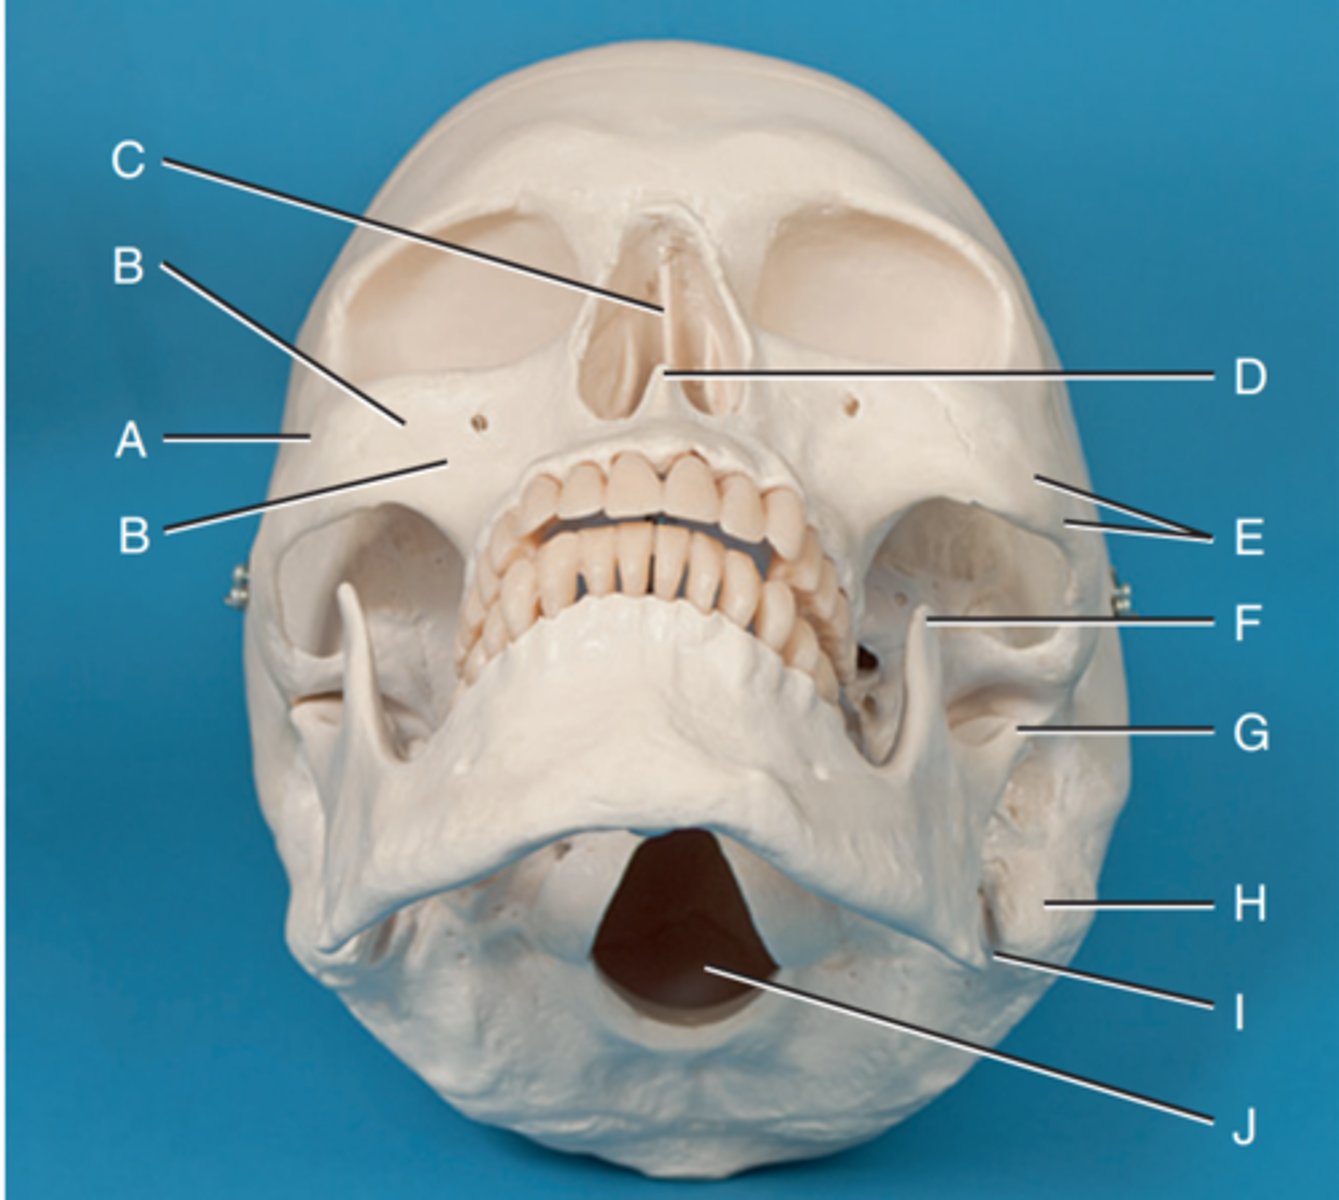

Zygomatic prominence

Label A

Body of maxilla

Label B

Bony nasal septum

Label C

Anterior nasal spine

Label D

Zygomatic arch

Label E

Coronoid process

Label F

Condyle

Label G

Mastoid process of temporal bone

Label H

Angle of mandible

Label I

Foramen magnum

Label J